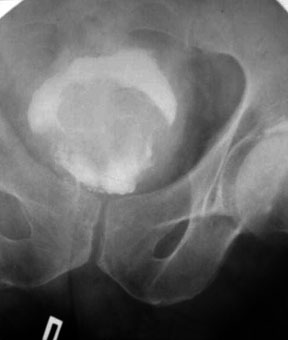

| Рис. 6.5. Прицельная рентгенограмма таза. Цистография. Определяется обширный дефект наполнения связанный со стенкой мочевого пузыря с неровными контурами. Рак мочевого пузыря. |